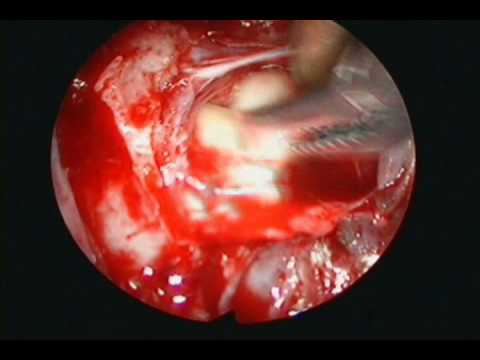

Zewnątrzoponowy ropień okolicy lędźwiowej

Na filmie zaprezentowano lewostronną hemilaminektomięna poziomie L4-L5 wykonaną w celu ewakuacji zewnątrzoponowego ropnia powstałego spontanicznie po stronie brzusznej worka oponowego. Operator po pobraniu...